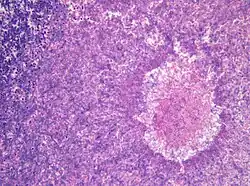

Histopathology of aspergilloma, H&E staining

Although most fungi—and especially Aspergillus—fail to grow in healthy human tissue, significant growth may occur in people whose adaptive immune system is compromised, such as those with chronic granulomatous disease, who are undergoing chemotherapy, or who have recently undergone a bone marrow transplantation. Within the lungs of such individuals, the fungal hyphae spread out as a spherical growth. With the restoration of normal defense mechanisms, neutrophils and lymphocytes are attracted to the edge of the spherical fungal growth where they lyse, releasing tissue-digesting enzymes as a normal function. A sphere of the infected lung is thus cleaved from the adjacent lung. This sphere flops around in the resulting cavity and is recognized on x-ray as a fungus ball. This process is beneficial as a potentially serious invasive fungal infection is converted into surface colonization. Although the fungus is inactivated in the process, surgeons may choose to operate to reduce the possibility of bleeding. Microscopic examination of surgically removed recently formed fungus balls clearly shows a sphere of dead lung containing fungal hyphae. Microscopic examination of older lesions reveals mummified tissue which may reveal faint residual lung or hyphal structures.[5]